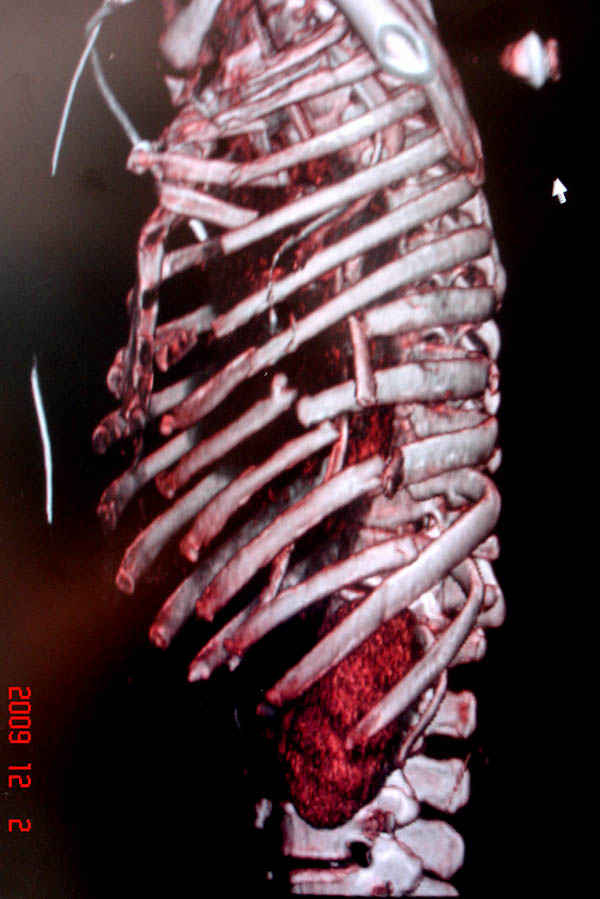

К нам поступила больная 56 лет после автоаварии в бессознательном состоянии, которая срочно заинтубирована в приемном отделении и сделаны необходимые исследования. Данные КТ и рентген показали перелом дистального бедра и Dissociation upper extremity - закрытый отрыв левой верхней конечности на уровне грудинно-ключичного сочленения и множественные переломы ребер.

На поверхности грудной клетки из-за полного разрыва грудной мышцы под кожей заметно биение сердца и след от ремня безопасности. Грудная клетка расширена из-за смещения верхней конечности вверх и латерально. Признаков васкулярного повреждения нет, и из-за отсутствия сознания не смогли определить наличия повреждения нервов.

На седьмые сутки нами совместно с торакальным хирургом сделана операция по фиксации грудинно-ключичного сочленения и переломов ребер.